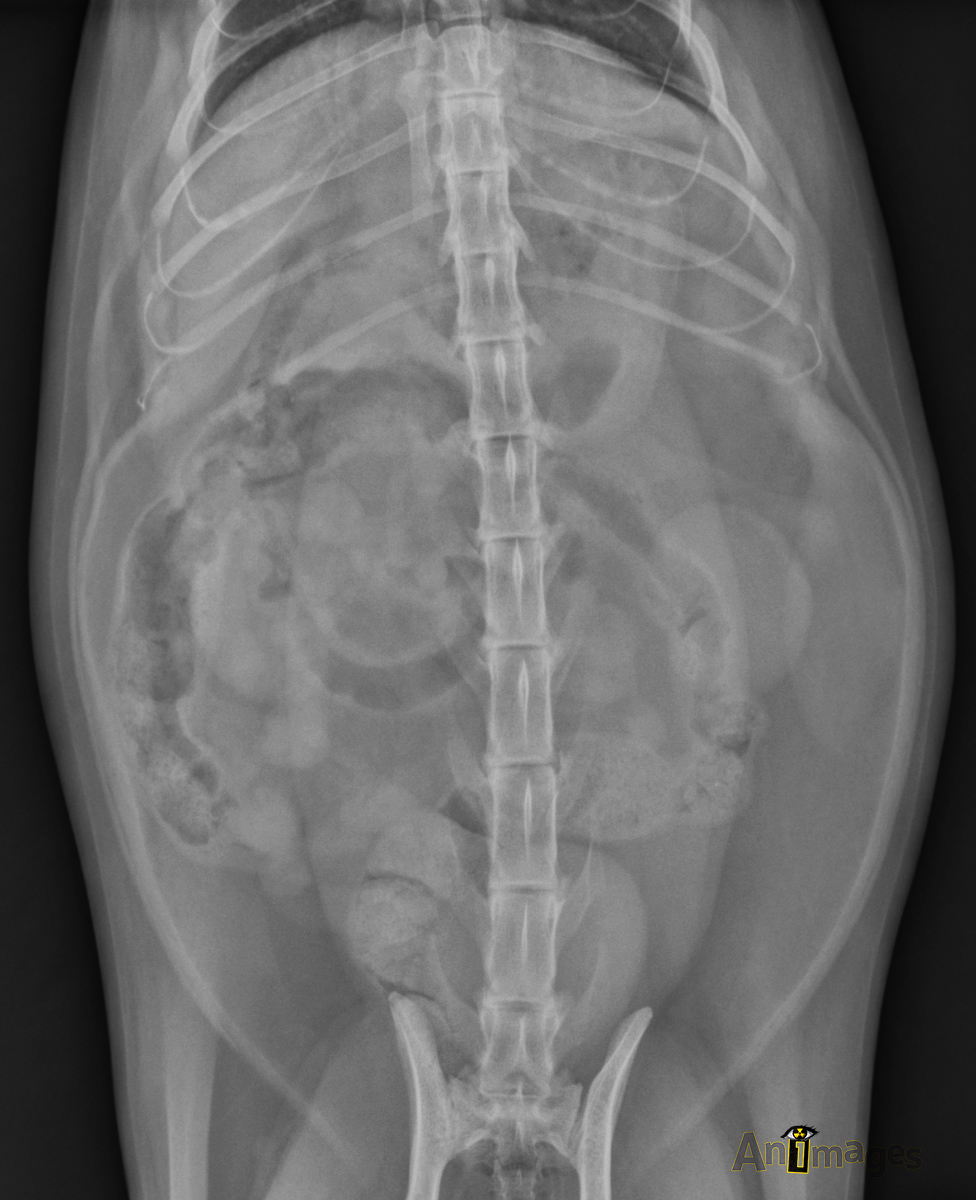

VD

Ventrodorsale